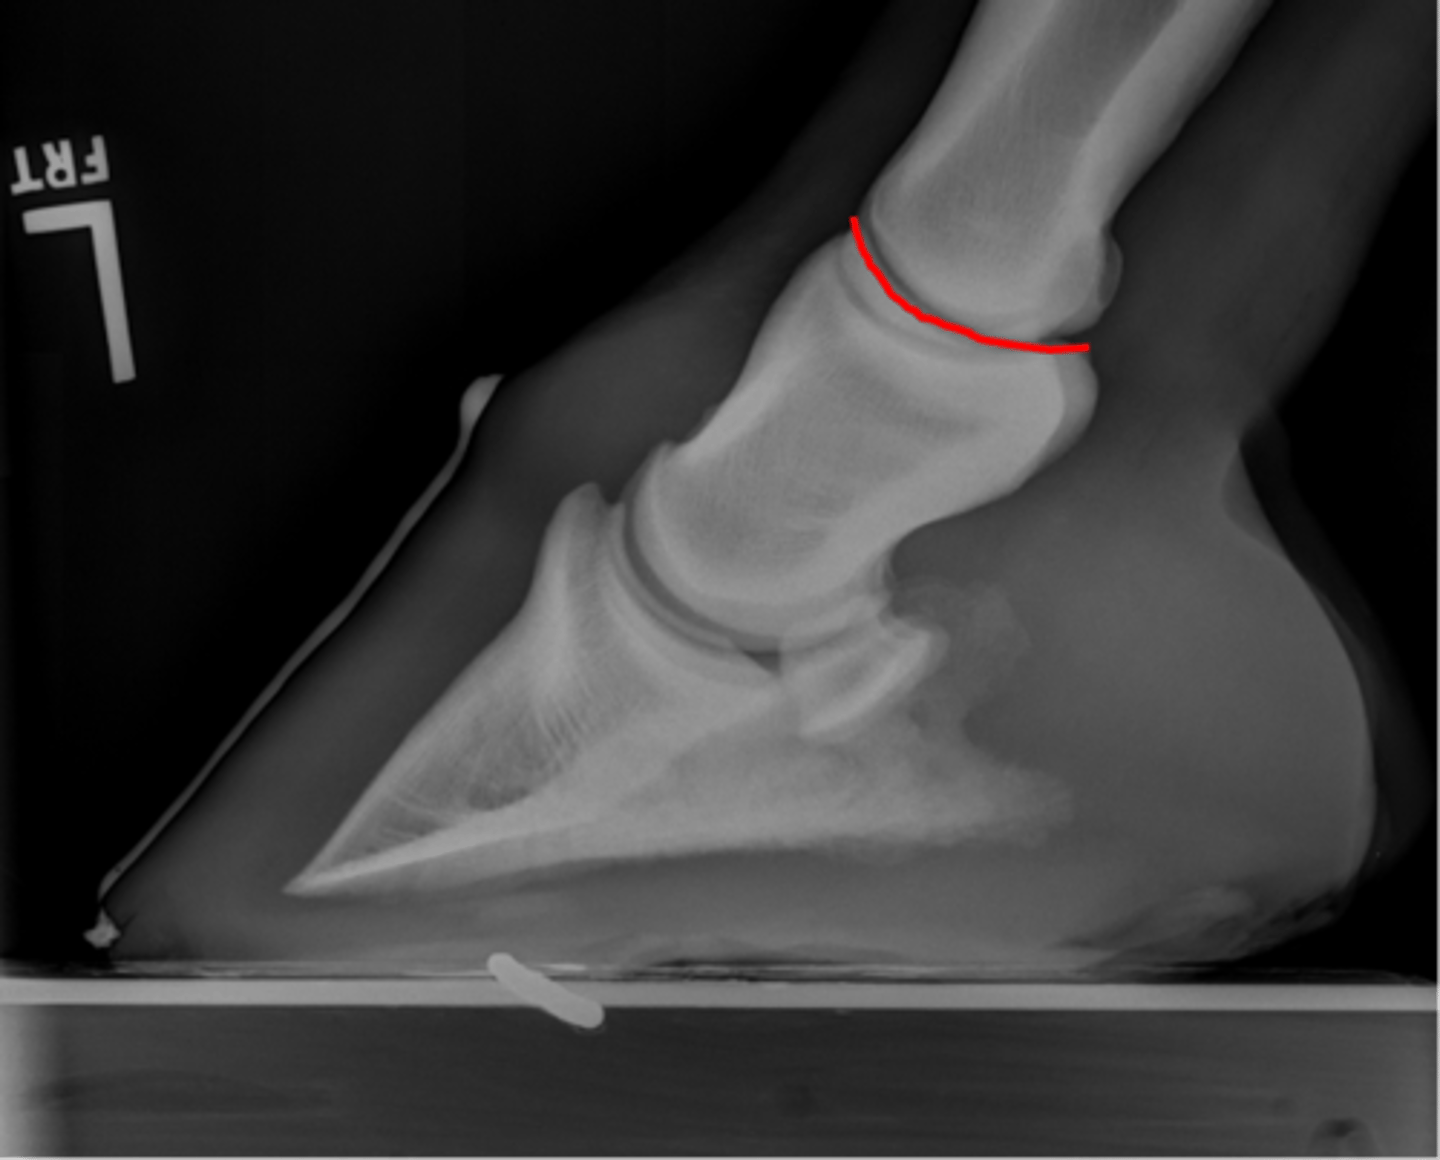

Coffin bone (P3)

Palmar process of P3

Extensor process of P3

Navicular bone

Coffin joint

Proximal interphalageal joint (pastern joint)

Short pastern (P2)

Upright pedal or high coronary

What view is this?